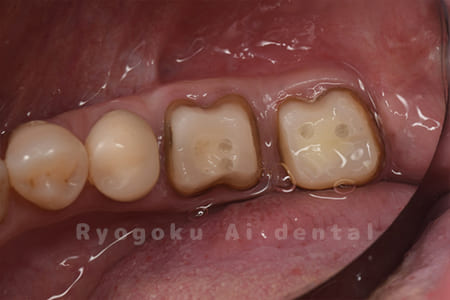

Case03

-

- 原因

- 重度縁下カリエス

- 治療期間

- 約2ヶ月(最終補綴装着まで含む)

- 治療内容

- クラウンレングスニング+歯周外科

- 治療費用

- 44,000円(最終補綴を除く)

他院で抜歯を宣告された患者様です。虫歯が歯茎の中まで及んでいたため、歯周外科・クラウンレングスニングを行い、保存を行いました。